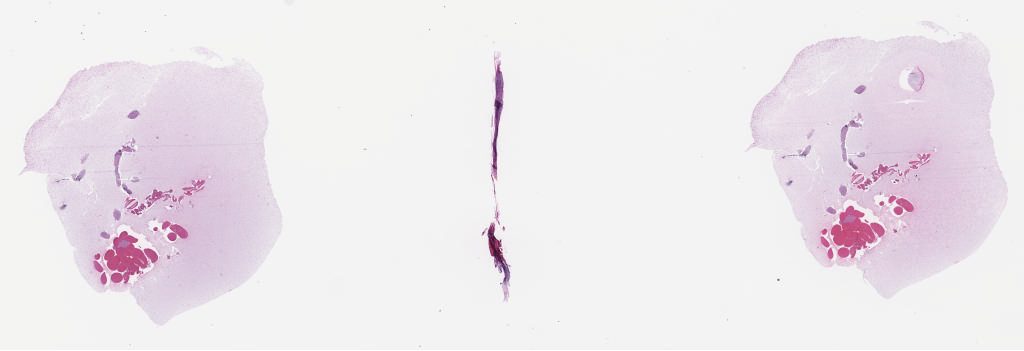

Pancreas Shark Core Biopsies 2021\Case 32

Case32a.svs

Case32b.svs